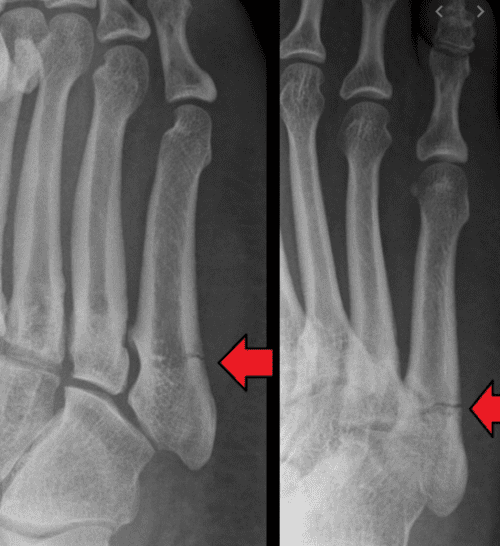

Jones Fracture FootEducation

From footeducation.com